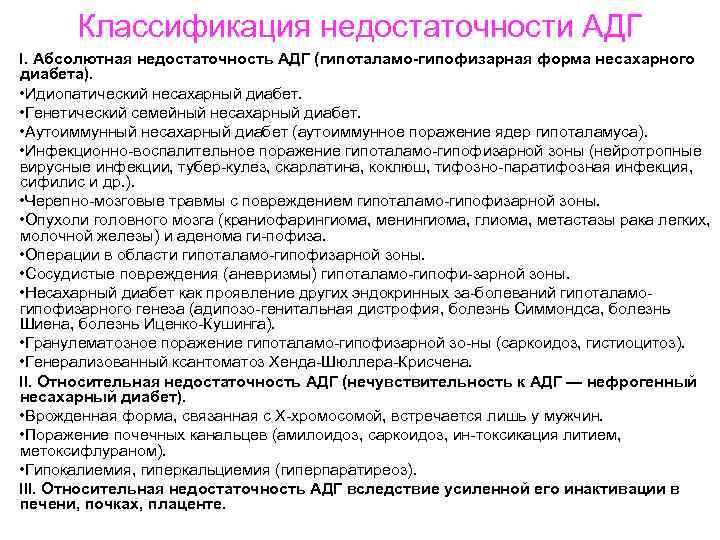

Классификация недостаточности АДГ I. Абсолютная недостаточность АДГ (гипоталамо-гипофизарная форма несахарного диабета). • Идиопатический несахарный диабет. • Генетический семейный несахарный диабет. • Аутоиммунный несахарный диабет (аутоиммунное поражение ядер гипоталамуса). • Инфекционно воспалительное поражение гипоталамо гипофизарной зоны (нейротропные вирусные инфекции, тубер кулез, скарлатина, коклюш, тифозно паратифозная инфекция, сифилис и др. ). • Черепно мозговые травмы с повреждением гипоталамо гипофизарной зоны. • Опухоли головного мозга (краниофарингиома, менингиома, глиома, метастазы рака легких, молочной железы) и аденома ги пофиза. • Операции в области гипоталамо гипофизарной зоны. • Сосудистые повреждения (аневризмы) гипоталамо гипофи зарной зоны. • Несахарный диабет как проявление других эндокринных за болеваний гипоталамо гипофизарного генеза (адипозо генитальная дистрофия, болезнь Симмондса, болезнь Шиена, болезнь Иценко Кушинга). • Гранулематозное поражение гипоталамо гипофизарной зо ны (саркоидоз, гистиоцитоз). • Генерализованный ксантоматоз Хенда Шюллера Крисчена. II. Относительная недостаточность АДГ (нечувствительность к АДГ — нефрогенный несахарный диабет). • Врожденная форма, связанная с Х хромосомой, встречается лишь у мужчин. • Поражение почечных канальцев (амилоидоз, саркоидоз, ин токсикация литием, метоксифлураном). • Гипокалиемия, гиперкальциемия (гиперпаратиреоз). III. Относительная недостаточность АДГ вследствие усиленной его инактивации в печени, почках, плаценте.

Классификация недостаточности АДГ I. Абсолютная недостаточность АДГ (гипоталамо-гипофизарная форма несахарного диабета). • Идиопатический несахарный диабет. • Генетический семейный несахарный диабет. • Аутоиммунный несахарный диабет (аутоиммунное поражение ядер гипоталамуса). • Инфекционно воспалительное поражение гипоталамо гипофизарной зоны (нейротропные вирусные инфекции, тубер кулез, скарлатина, коклюш, тифозно паратифозная инфекция, сифилис и др. ). • Черепно мозговые травмы с повреждением гипоталамо гипофизарной зоны. • Опухоли головного мозга (краниофарингиома, менингиома, глиома, метастазы рака легких, молочной железы) и аденома ги пофиза. • Операции в области гипоталамо гипофизарной зоны. • Сосудистые повреждения (аневризмы) гипоталамо гипофи зарной зоны. • Несахарный диабет как проявление других эндокринных за болеваний гипоталамо гипофизарного генеза (адипозо генитальная дистрофия, болезнь Симмондса, болезнь Шиена, болезнь Иценко Кушинга). • Гранулематозное поражение гипоталамо гипофизарной зо ны (саркоидоз, гистиоцитоз). • Генерализованный ксантоматоз Хенда Шюллера Крисчена. II. Относительная недостаточность АДГ (нечувствительность к АДГ — нефрогенный несахарный диабет). • Врожденная форма, связанная с Х хромосомой, встречается лишь у мужчин. • Поражение почечных канальцев (амилоидоз, саркоидоз, ин токсикация литием, метоксифлураном). • Гипокалиемия, гиперкальциемия (гиперпаратиреоз). III. Относительная недостаточность АДГ вследствие усиленной его инактивации в печени, почках, плаценте.